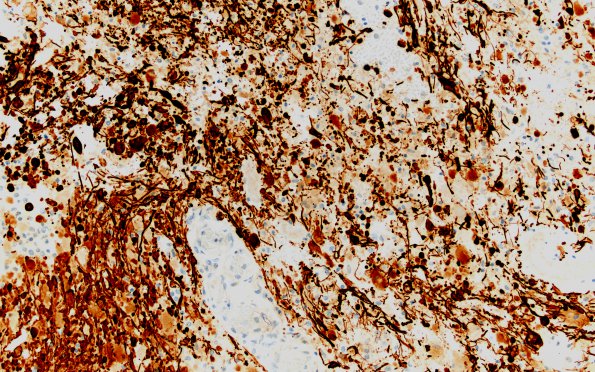

4C2 Astrocytoma, pilocytic (Case 4) GFAP 20X

Mostly spindled residual pilocytic tumor with endothelial proliferation (GFAP IHC)